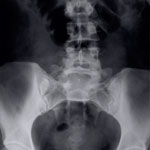

- X-ray

An X-ray is a diagnostic test that uses radiation waves, called x-rays, to take pictures of your body tissues. It is used to detect bone fractures, arthritis, scoliosis, tumors, osteoporosis, fluid in the lungs, and infection. In the spine, flexion and extension x-rays can help detect alignment of the bones.